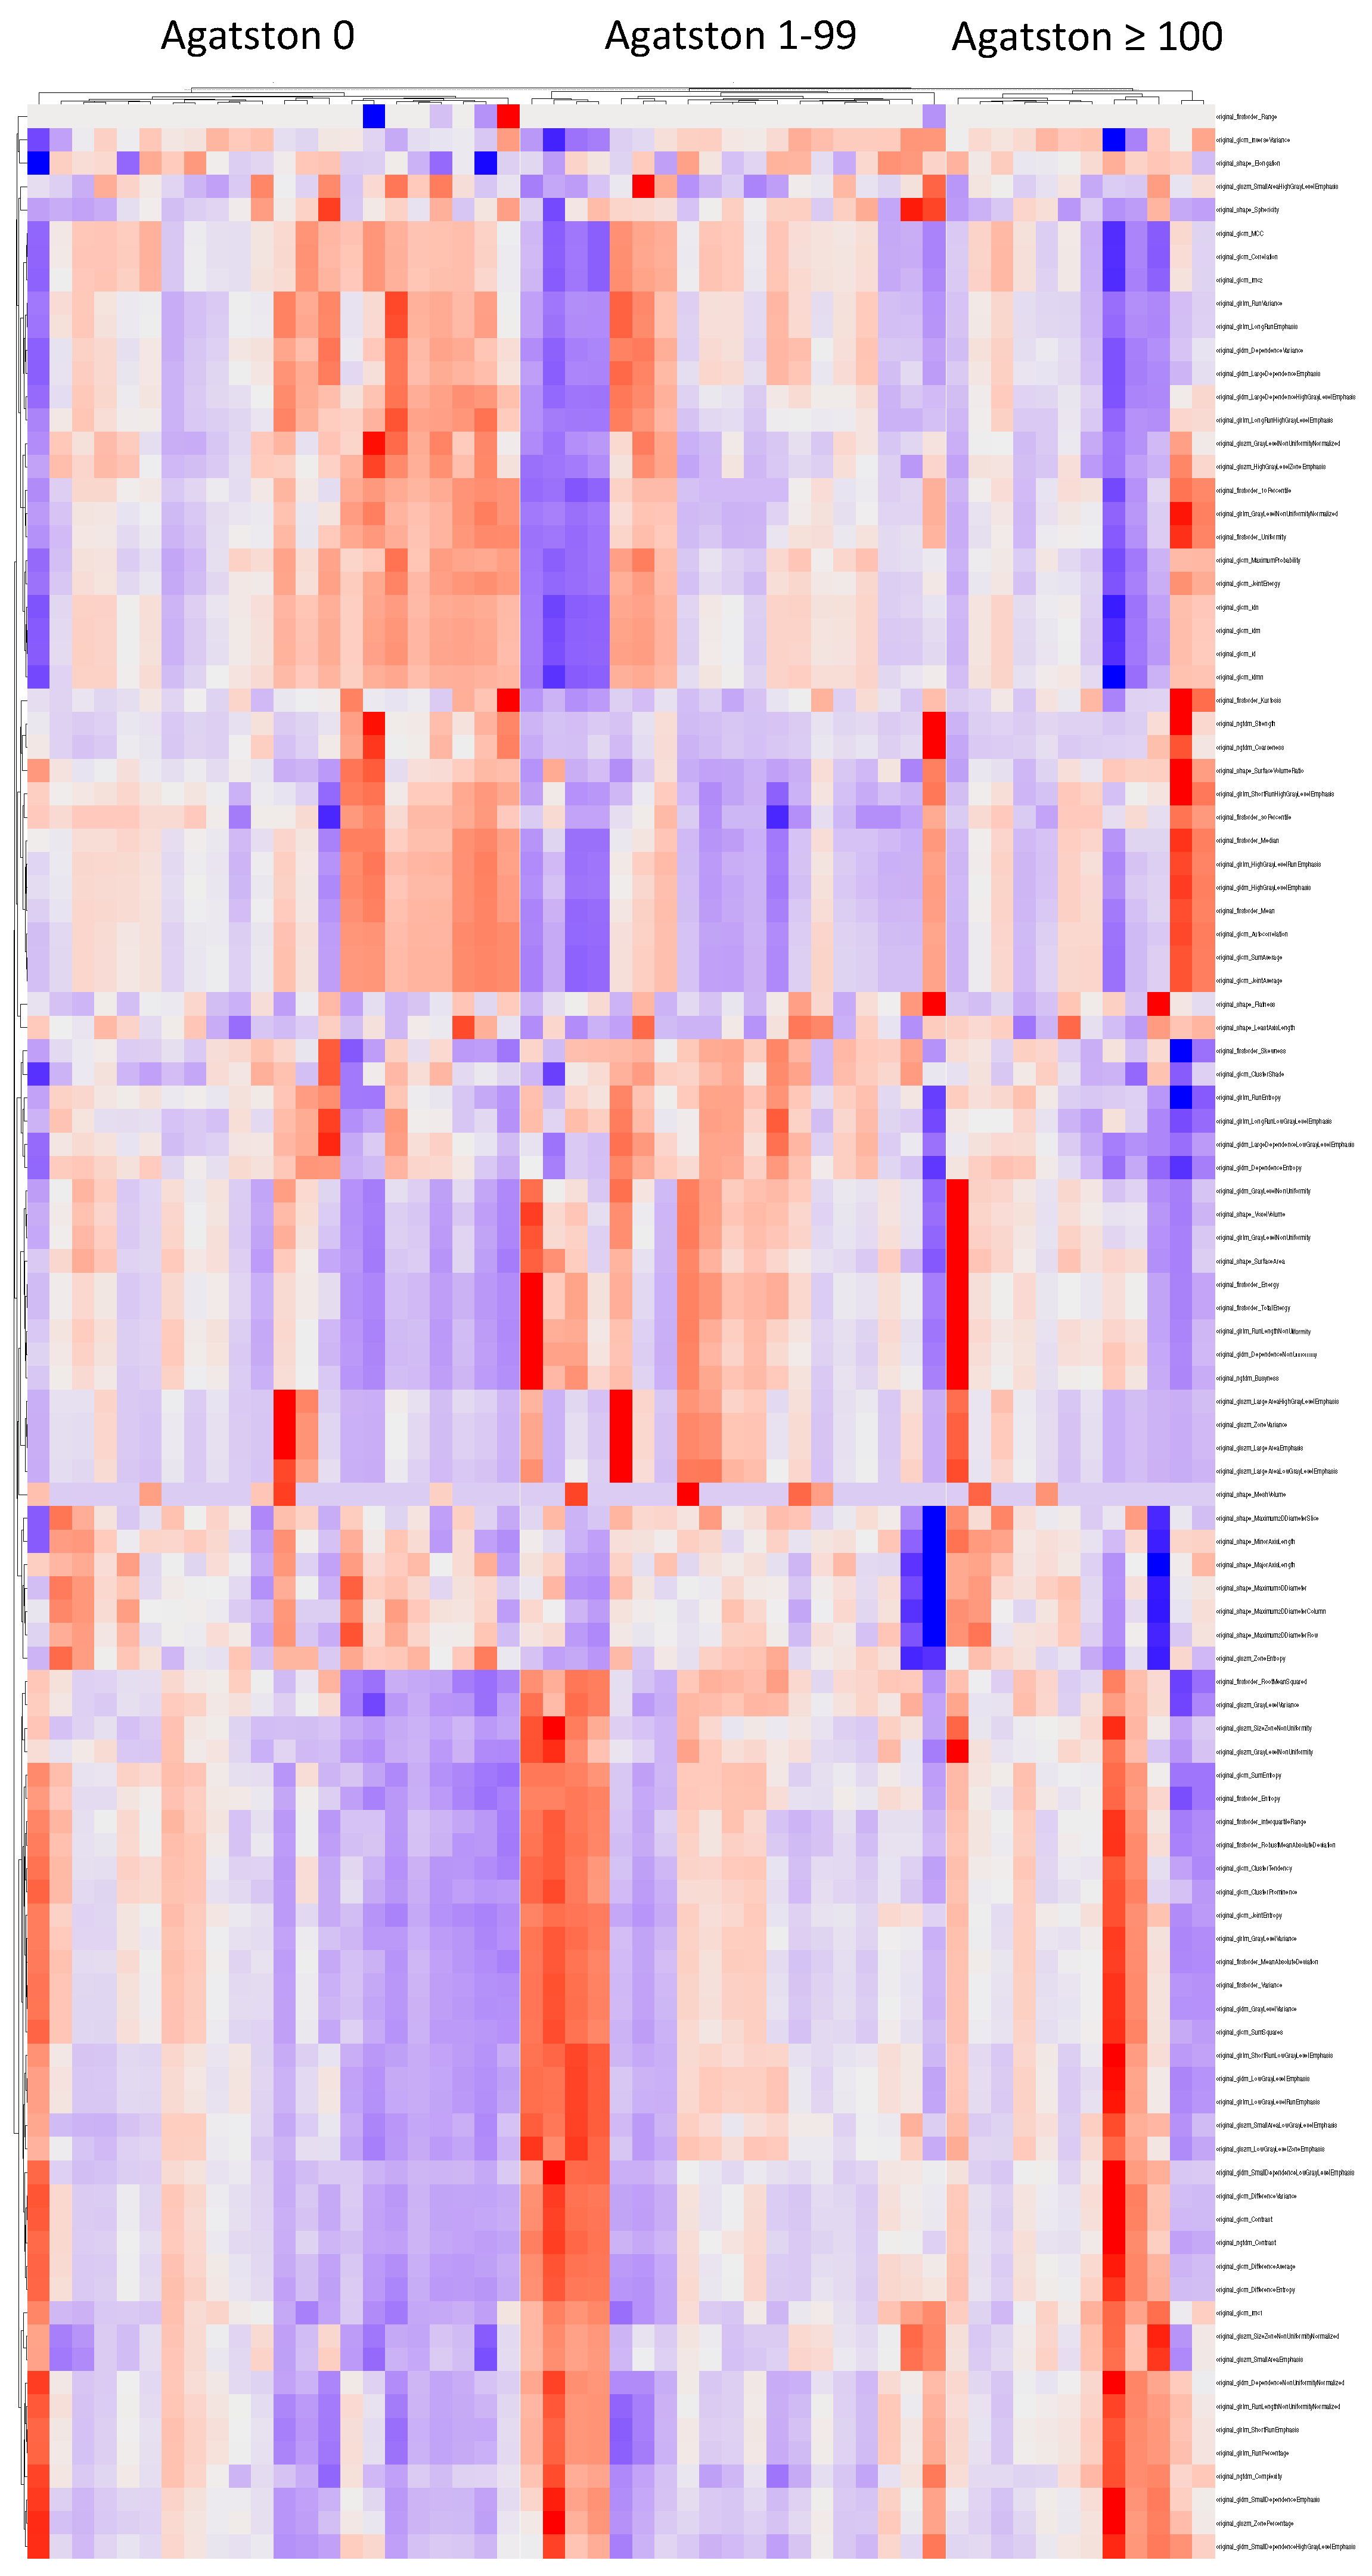

3.2. Cluster Analysis

3.3. Feature Selection